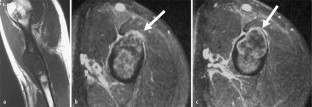

MRI morphology of bone tumors and tumor-like lesions

Für das Staging und die Charakterisierung von Knochentumoren und tumorähnlichen Läsionen ist in der Magnetresonanztomographie (MRT) der Einsatz von Spinechosequenzen erforderlich. Die MRT hat nur einen geringen Stellenwert in der Bestimmung der Dignität. Obwohl viele Knochentumoren und tumorähnliche Läsionen eine vergleichbare Morphologie in dieser bildgebenden Modalität aufweisen, können einige Tumorentitäten mittels MRT recht zuverlässig diagnostiziert werden. Hierzu zählen Knorpeltumoren, die solitäre und aneurysmatische Knochenzyste, der Riesenzelltumor, fetthaltige Läsionen und bis zu einem gewissen Grad auch das Osteoidosteom und das Osteoblastom. Es werden praktische Tipps gegeben, wann bei Tumorverdacht die MRT eingesetzt werden sollte, wie bei einem zufällig bei einer MRT gefundenen Tumor die Untersuchung modifiziert werden sollte und welcher Tumor vorliegen könnte.

Spin-echo sequences are mandatory at MRI for staging and characterization of bone tumors and tumor-like lesions. MRI is of minor value in the estimation of the malignant potential of an osseous lesion. Although many bone tumors and tumor-like lesions present similar morphology at MRI, some entities can be diagnosed with good reliability. These include chondrogenic tumors, solitary and aneurysmal bone cysts, giant cell tumors, lesions containing fatty tissue and, to a certain extent, osteoid-osteomas and osteoblastomas. Practical advice is given regarding when to perform a MRI study in cases of tumor suspicion. Further advices are given for cases a tumor is found incidentally at a MRI study, how to modify the study and which kind of tumor may be present.